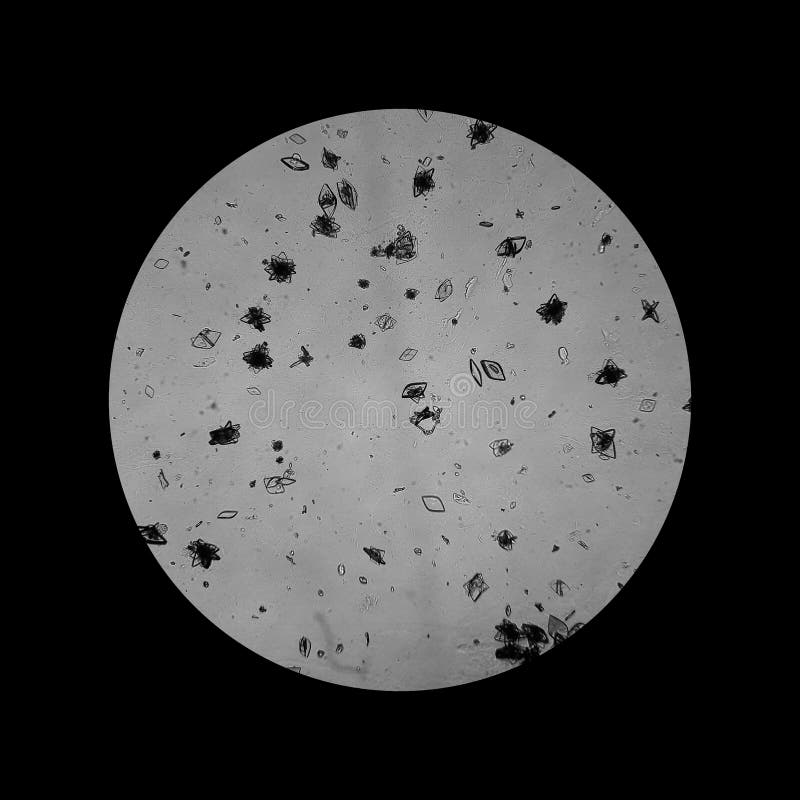

Microscopic Examination Of Urine Sediment Dehydration Urine Sediment dehydration also places you more at risk of kidney stones, which can cause sediment in the urine. It doesn’t always mean you have an infection. a good intake of water can treat sediment caused by dehydration. a high specific gravity represents concentrated urine and may indicate dehydration or increased levels of solutes in the urine. You can. Dehydration Urine Sediment.

Identifying Crystals in the Urinary Sediment — swissnephro Dehydration Urine Sediment a good intake of water can treat sediment caused by dehydration. a high specific gravity represents concentrated urine and may indicate dehydration or increased levels of solutes in the urine. Healthcare providers can prescribe antibiotics that can treat the sediment for. A value of less than 1.010 indicates relative hydration, and a value greater than 1.020. normal. Dehydration Urine Sediment.